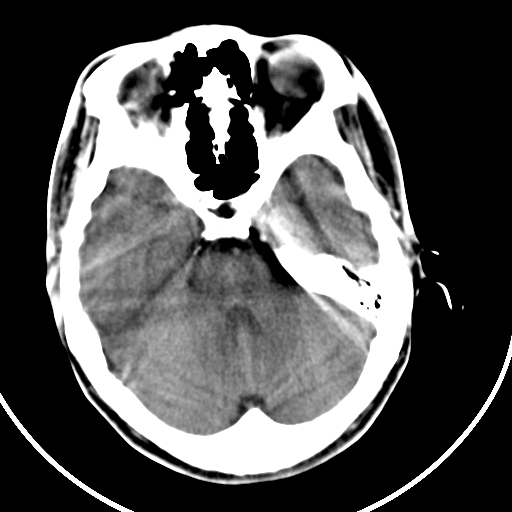

标题: CT21939:男20岁,外伤一年后,现头疼. [打印本页]

标题: CT21939:男20岁,外伤一年后,现头疼.

颅骨凹陷性骨折并压迫脑组织致大脑镰下疝!

是硬膜外血肿机化还是陈旧性凹陷性骨折?

硬膜外血肿机化

结合文献报道,考虑血肿继发改变,血肿骨化?

如果是骨折,外板正常内板这么明显凹陷,请问这样的骨折是怎样形成的?形成的机理是什么?有没有可能形成?

硬膜外血肿伴包膜钙化

左侧额部硬膜外血肿机化、骨化。

左侧额部硬膜外血肿机化、骨化